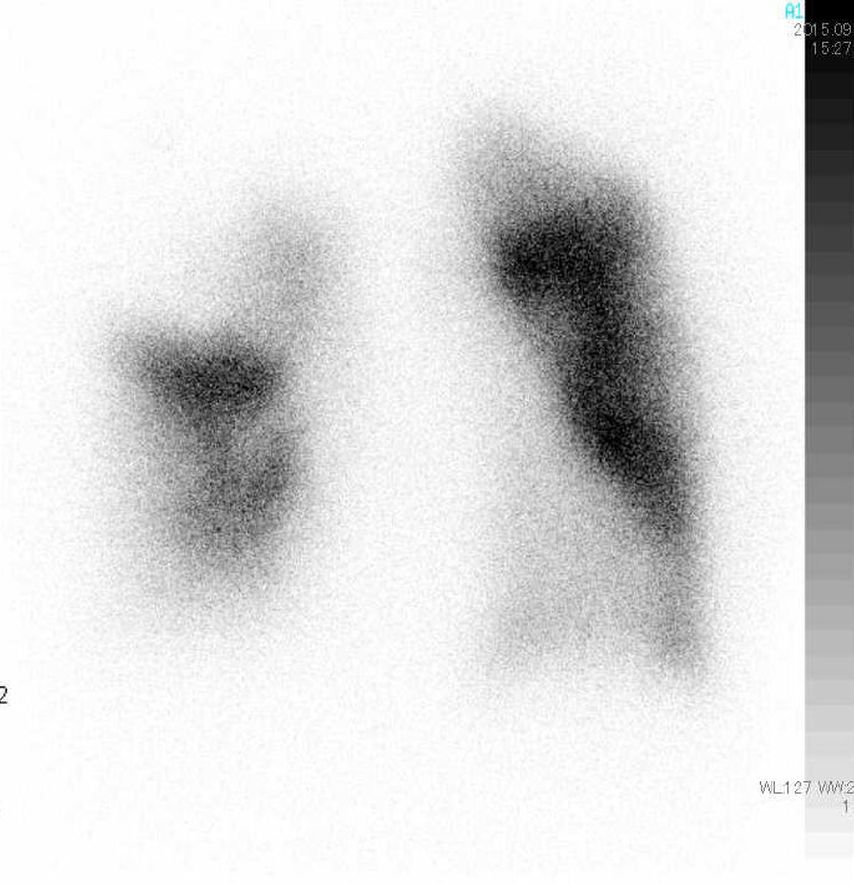

Spirometrie (Abb. 1) und DLCO (Diffusionskapazität für Kohlenmonoxid) helfen zur Erkennung von COPD, interstitiellen Lungenerkrankungen oder Hypoventilationssyndromen. Hochauflösende CT-Thoraxuntersuchungen sind unerlässlich zur Erkennung von parenchymatösen Lungenerkrankungen, Emphysem und Fibrose. Ventilations-/Perfusions-Scan (V/Q-Scan) ist empfohlen bei allen Patienten mit Verdacht auf PH zum Screening auf CTEPH, da eine hohe Sensitivität für Perfusionsdefekte besteht (Abb. 2). CT-Lungenangiografie (CTPA) liefert anatomische Details bei Verdacht auf CTEPH oder akute Lungenembolie. Die Schwäche der CTPA ist ihre schlechte Auflösung in distalen kleinen Gefäßen.

Abb. 2: Anterior-posteriores Projektions-Bild einer Perfusionsszintigraphie bei Chronisch Thromboembolischer Pulmonaler Hypertension (CTEPH). Es zeigen sich typische keilförmige Defekte. Die dazugehörige Ventilationsszintigraphie ist normal, und wird oft übersprungen. Die Perfusionsszintigraphie ist der sensitivste Screeningtest für CTEPH, beweist aber die Erkrankung nicht.